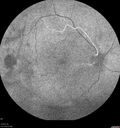

PDR and Vitreous hemorrhage - Second FA is following PRP laser265 views42 year old man (date 2018): Prior to 2 months ago the vision in the right eye was good. This started with a glob in the vision and then the vision got better. Then the string came back down and is getting bigger and bigger. The last time he had bleeding in the left eye he had surgery in 2009. The left eye is now doing OK other than there is a cataract. The right eye had some laser treatment done in 2009. The vitrectomy and laser were done at William Beaumont.

VA OD: sc3'/200 NscUnable

VA OS: sc20/40 NscJ2-1